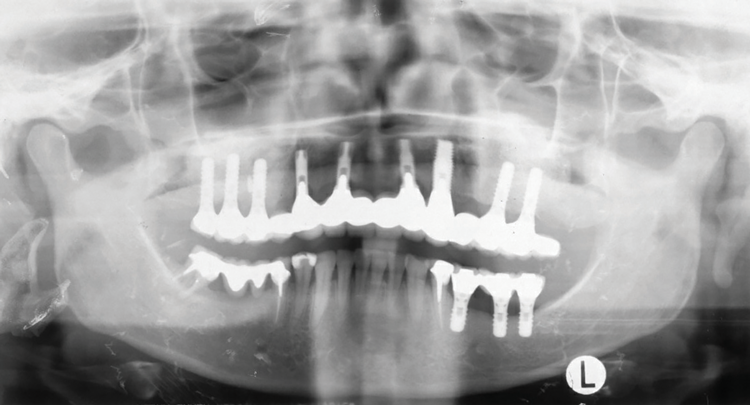

Fig 18. Panoramic radiograph at 20-year follow-up.

Figure 18

In 2020, the patient presented to the NYUCD Periodontology and Implant Dentistry Clinic. A clinical examination and radiographic evaluation showed that the patient's maxillary arch still exhibited good peri-implant soft-tissue health and stable marginal bone level with slight bone loss on implants Nos. 2, 6, 8, and 11 (Figure 18 through Figure 20). The maxillary prosthesis showed adequate stability with a slight chipped suprastructure on the porcelain on the right side. The patient was advised to substitute the implant-supported, screw-retained hybrid acrylic complete denture in the maxilla with a fixed, implant-supported, screw-retained prosthesis, which she declined due to financial considerations.